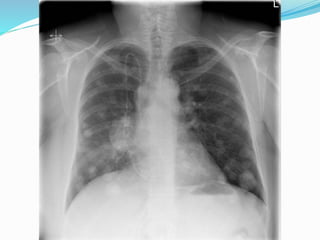

Findings on Chest X-ray

Findings on ChestX-ray  Nodule (< 3cm) vs. Mass (>= 3cm)  Location:  Peripheral (Adenocarcinoma) vs  Central (Squamous)  Single or multiple (metastases)  Atelectasis of lobe or lung  Pneumonia  Hilar and mediastinal adenopathy  Pleural effusions